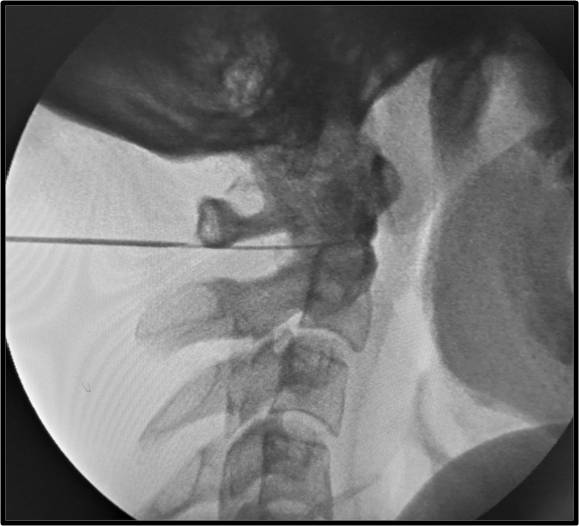

Πρόκειται για την έγχυση μικρής ποσότητας στεροειδούς στην ατλαντοϊνιακή ή στην ατλαντοαξονική άρθρωση της ανώτερης αυχενικής μοίρας κάτω από ακτινοσκοπική καθοδήγηση. Η ανάπτυξη αρθρίτιδας ή ο τραυματισμός των αρθρώσεων αυτών μπορεί να αποτελεί πηγή χρόνιου σοβαρού πόνου στην αυχενοϊνιακή χώρα.